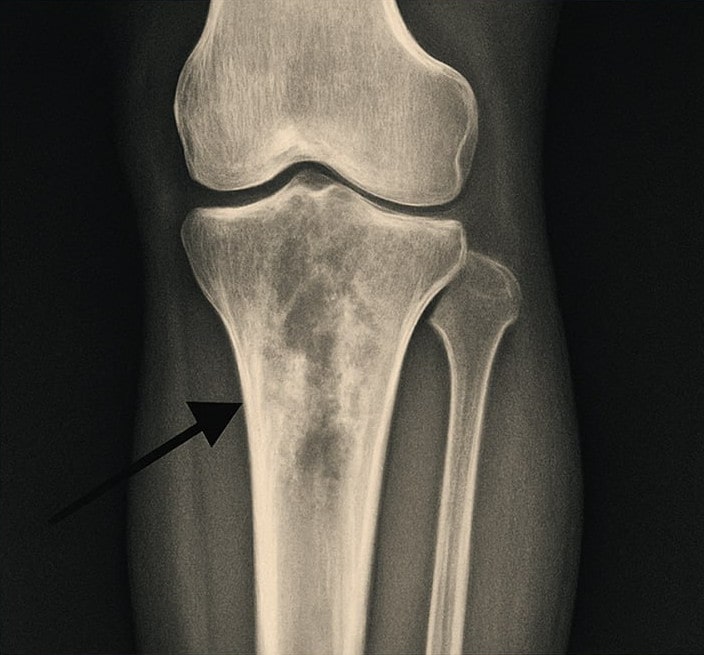

Важным этапом диагностики является визуализация пораженной области. Рентгенография позволяет выявить изменения в костной ткани, однако на ранних стадиях остеомиелит может не проявляться на снимках. В таких случаях могут быть рекомендованы более современные методы, такие как магнитно-резонансная томография (МРТ) или компьютерная томография (КТ), которые обеспечивают более детальную информацию о состоянии костей и окружающих мягких тканей. В некоторых случаях требуется биопсия костной ткани для подтверждения диагноза и определения конкретного патогена.